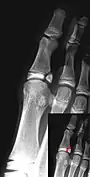

Salter–Harris III fracture of big toe proximal phalanx.